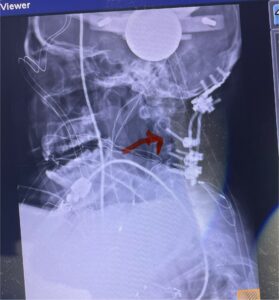

Cervical x-rays revealed a significantly increased atlanto-axial interval (Fig. 5) On review of her imaging studies it was noted that the right C2 isthmus was very thinned by the vertebral foramen (Figs 6a, b, and c) which would make an attempt at placing a C2 pars screw dangerous. A decision was made to perform an occipital-cervical fusion because only possible unilateral fixation and an extensive C1 laminectomy to be performed eliminating a fixation point if a more traditional C1-C2 was performed. Even if C1 lateral mass screws were able to be placed one could only perform a unilateral screw construct fixation to C2. We performed an occipital cervical fusion down to C4 to get enough inferior fixation and C1 laminectomy. The decompression went well. We placed a left unilateral pars screw and bilateral C3 and C4 lateral mass screws. We placed three 12 mm screws in the midline keel (Fig. 7). Postoperatively the patient had all around improvement in her symptoms and did not qualify for rehab. Her post op films at 6 weeks (Fig. 8)

Fig. 8: Intraoperative photograph demonstrating occipital-cervical construct and C1 laminectomy (blue dot). Note the 3 screws in the midline keel (blue arrow)